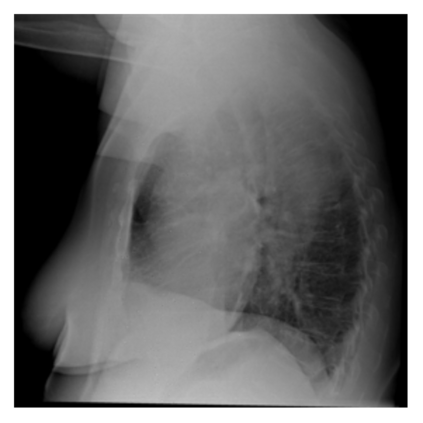

The evaluation of infectious disease processes on radiologic images is an important and challenging task in medical image analysis. Pulmonary infections can often be best imaged and evaluated through computed tomography (CT) scans, which are often not available in low-resource environments and difficult to obtain for critically ill patients. On the other hand, X-ray, a different type of imaging procedure, is inexpensive, often available at the bedside and more widely available, but offers a simpler, two dimensional image. We show that by relying on a model that learns to generate CT images from X-rays synthetically, we can improve the automatic disease classification accuracy and provide clinicians with a different look at the pulmonary disease process. Specifically, we investigate Tuberculosis (TB), a deadly bacterial infectious disease that predominantly affects the lungs, but also other organ systems. We show that relying on synthetically generated CT improves TB identification by 7.50% and distinguishes TB properties up to 12.16% better than the X-ray baseline.